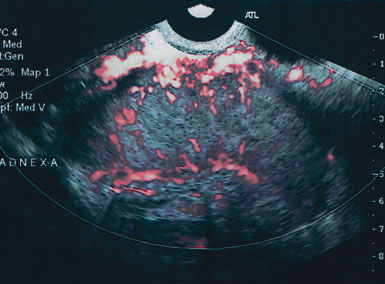

Fig. 5. A highly vascular 8 × 6-cm solid mass in this postmenopausal patient was a Stage III poorly differentiated adenocarcinoma.